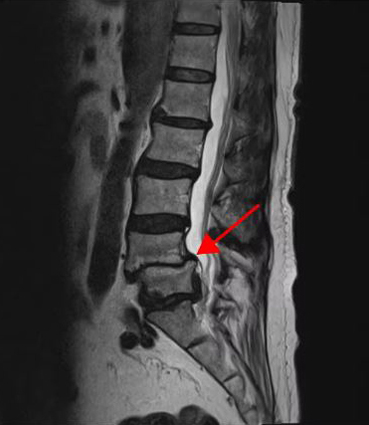

<4-5번 척추전방전위증>

이 환자분은 요추 4-5번 오른쪽에 심한 추간공협착증, 2단계의 전방전위증이 있으며, 특히 전방전위증으로 인해 추간공이 매우 좁아져 있습니다. 또 요추 5-1번 왼쪽에 디스크 파열이 있습니다.